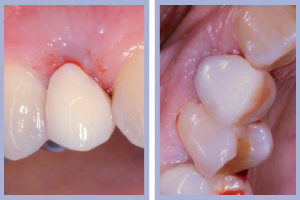

Il posizionamento implantare è stato seguito dal posizionamento e dalla preparazione intra-orale dei monconi temporanei e dalla successiva consegna, previa ribasatura, delle corone provvisorie. Durante la fase di attesa dell’osteointegrazione degli impianti si procedeva alla preparazione protesica dei canini (nella posizione dei laterali) per ottenere, tramite ricopertura protesica, la forma degli incisivi laterali.

- Figg. 15a, b – Inserimento e preparazione del moncone temporaneo di destra

- Figg. 16a, b – Consegna della corona provvisoria in resina di destra

- Figg. 17a, b – Inserimento e preparazione del moncone temporaneo di sinistra

- Fig. 18 – Consegna della corona provvisoria in resina di sinistra